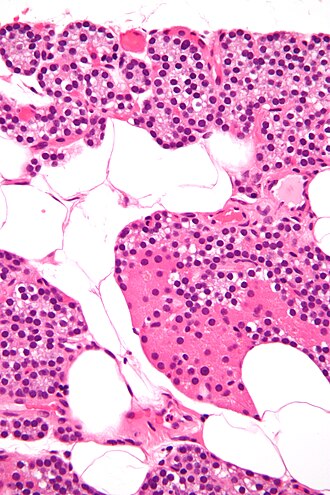

Microscopic

Features:[17]

- Low power:

- May vaguely resemble lymphoid tissue - may have hyperchromatic cytoplasm.

- Does not have follicular centres like a lymph node.

- May form gland-like structure and vaguely resemble the thyroid at low power.

- Cytoplasm may be clear[18] - key feature.

- Surrounded by a thin fibrous capsule.

- High power:

- Mixed cell population:[19]

- Chief cells - predominant cell type, small, cytoplasm has variable staining (hyperchromatic-clear-eosinophilic).

- Oxyphil cells (acid staining cells[20]) - abundant cytoplasm.

- Adipocytes - dependent on age, body habitus, PT hormone, size of gland.[21]

- Increased with age, may be used to help differentiate from thyroid - key feature.